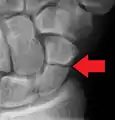

| An X-ray showing a fracture through the waist of the scaphoid | |